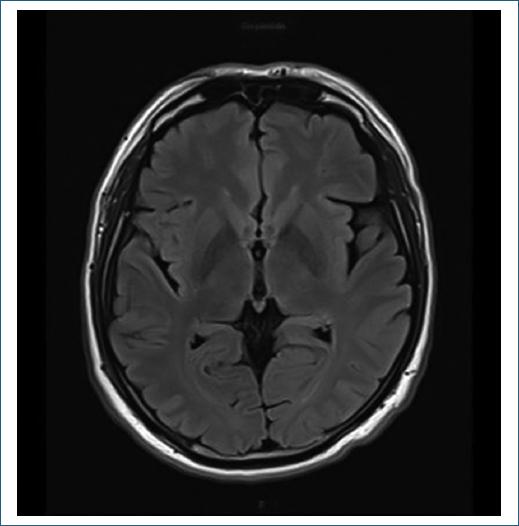

La resonancia magnética de encéfalo descarta lesiones estructurales evidentes (Fig. 1). Se realiza una punción lumbar con análisis citoquímico de LCR que muestra los siguientes resultados: células 0 (0-1/mm3), proteínas 32 mg/dl (15-45 mg/dl) y glucosa 76 mg/dl (sérica 98 mg/dl). El VDRL en sangre y en LCR es positivo.